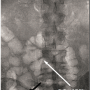

Retrieval. Our patient underwent venous color-flow duplex ultrasound scanning of the lower extremities to rule out lower extremity DVT before filter retrieval. IVC filter retrieval was performed in the catheterization laboratory under aseptic conditions via right femoral vein approach as the patient’s weight had decreased to 498 lb and was within table weight limits. A 12 Fr sheath was placed, and a pigtail catheter (Cordis Corporation) was used for imaging (Figure 2). Vena cavography was performed before retrieval, which did not reveal any trapped emboli or thrombi within the IVC filter. Repeat vena cavography was performed after retrieval of the filter with a snare to evaluate IVC patency.